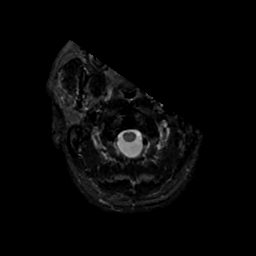

MR Study #17, July 7, 1991 -- Slice #0

[Home][Help][Clinical][Tour 1][Tour 2] Slice 0